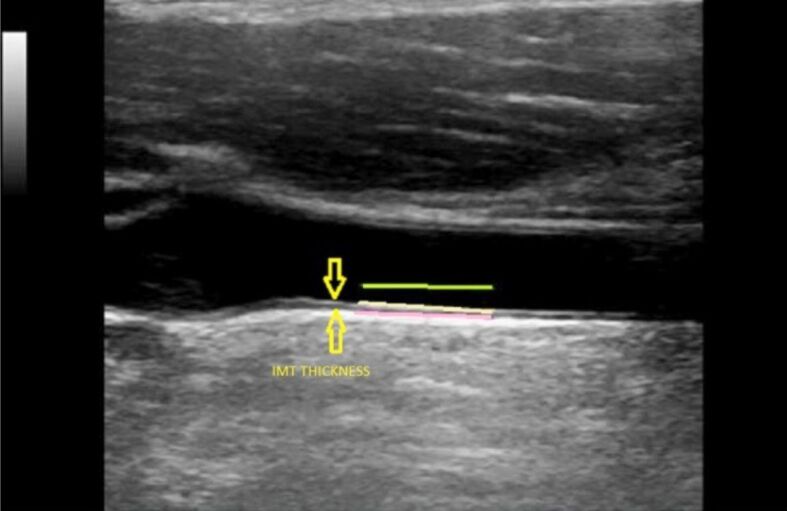

Patients, materials and methods: We conducted a prospective study on 168 patients diagnosed with chronic HCV infection or HCV-related cirrhosis. They were all treated with DAAs, with sustained virological response (SVR). Laboratory data, vibration-controlled transient elastography (VCTE), carotid intima-media thickness (IMT) measurement, and ankle-brachial index (ABI) were recorded in all patients.

Results: We found an average IMT of 1.22±0.2 mm, with a variance range from 1.14±0.19 mm in the mild and moderate fibrosis (≤F2) group to 1.29±0.25 mm in the severe fibrosis (≥F3) group. Also, patients with severe fibrosis (≥F3) present a more critical decrease of IMT values, with the carotid thickness affecting only 18.2% of individuals in the follow-up period. At the baseline, the best values of ABI were recorded in patients having F1-F2 fibrosis stage (mean value 1.02±0.19). Instead, in the group with severe fibrosis, the average value of ABI was lower (0.91±0.16) at the baseline, with a significant increase at SVR evaluation (p<0.001).